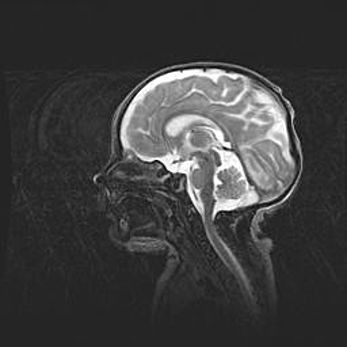

Наружная гидроцефалия с возможной атрофией височных областей.

Возраст: 28 дней

Вес: 3670 г

Пол: мужской

Окружность головы: 38 см

Срок гестации: 40 недель

Гидроцефалия головного мозга у новорожденных – это заболевание, которое характеризуется скоплением избыточного количества спинномозговой жидкости в желудочковой системе головного мозга в результате затруднения её перемещения от места выработки к месту поглощения в кровеносную систему или вследствие нарушения абсорбции. При открытой наружной форме гидроцефалии у новорожденных расширяются и переполняются субарахноидные пространства.

При нормотензивных  формах,  которые,  как  правило,  являются  следствием  перенесенных ишемических  повреждений  паренхимы  мозга,  возможно  сочетание микроцефалии  с нормотензивной гидроцефалией. В основе данных изменений лежит атрофия больших полушарий с преимущественной  локализацией  в  лобно-височных  областях.